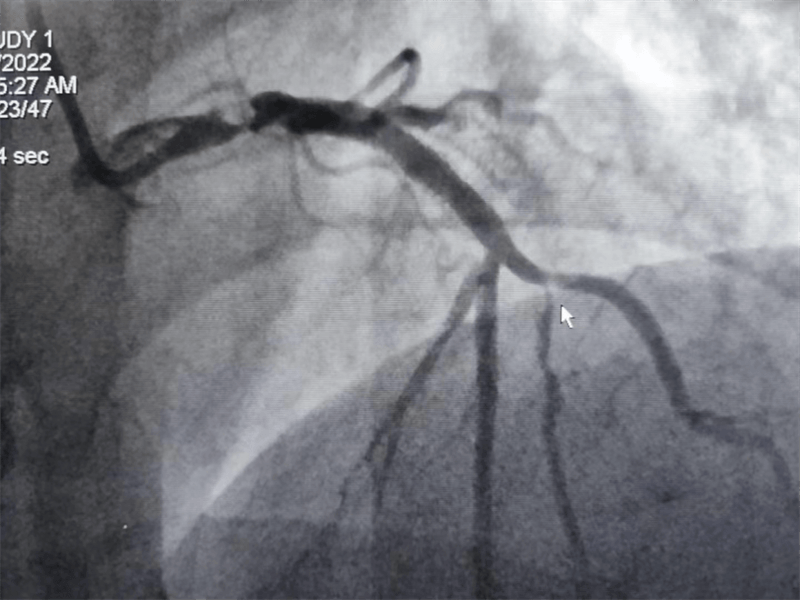

63岁的张大伯因严重心绞痛住院,心电图可见明显明显心肌缺血。主治医师黄永涛向患者讲明病情后,征得患者和家属同意,行冠脉造影检查。真是不做不知道,一做吓一跳。

冠脉造影结果提示:左主干末端及前降支开口处99%狭窄,回旋支开口处80-90%狭窄,中段支架内100%闭塞。看到造影结果时,在场医护人员无不惊出一身冷汗:左主干病变“细”如发丝——生死一线牵!患者拒绝搭桥手术,所以选择介入处理该病变。

我们结合患者病变特点,对回旋支支架内闭塞病变处药物球囊治疗,左主干病变植入1枚支架,术后,造影显示左主干病变处支架植入状态良好,血管内超声显示支架贴壁良好,患者血压、心率稳定,症状完全缓解,并安全返回重症监护室进一步治疗,术后张大伯无明显不适,生命体征稳定,病情明显好转。